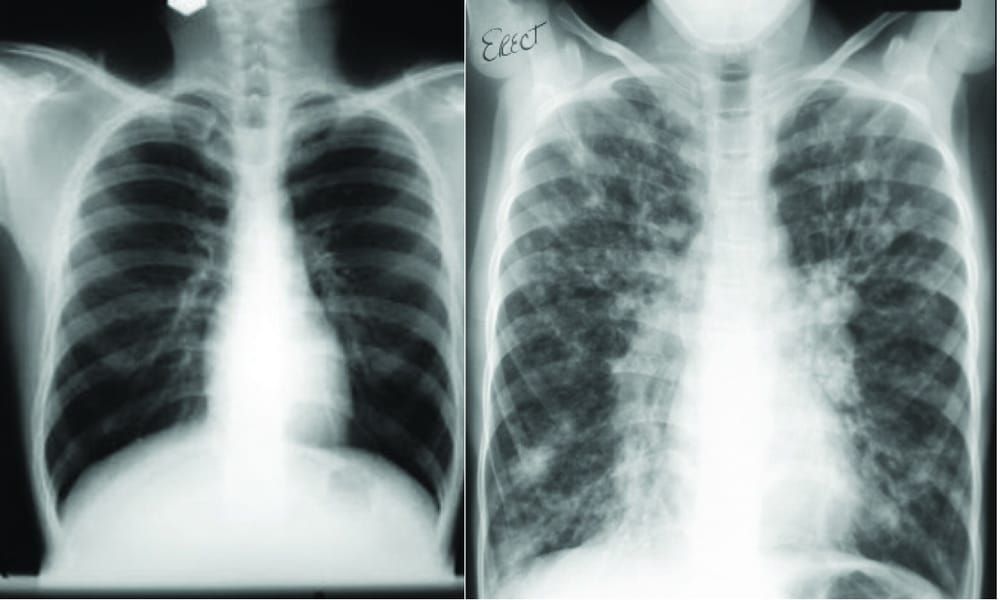

JD: CF is a genetically inherited disease, so if a patient has two copies of the abnormal gene then the cells lining the organs of their body don’t handle salt well. The mishandling of the salt leads to dehydration of the surface secretions – particularly in the lungs – so they become dry and sticky. They then act as a very attractive place for bugs and viruses entering the body. This triggers an inflammatory response, but the infection is never properly cleared, so you enter a vicious cycle of chronic infection and inflammation which leads to tissue damage and other difficulties.

JD: Well I don’t know that first hand, so no matter how well I know my patients I can never pretend to know exactly how they feel. It is certainly very difficult both practically and psychologically though. Practically, a huge amount has to be done every day to manage the disease – up to an hour a day of physiotherapy to clear mucous from the lungs, as well as nebuliser treatments and between ten and twenty different pills to be taken. That’s when things are going well, and almost all patients go through episodes where they need to be in hospital for several weeks at a time. Psychologically, it’s completely relentless and it’s something that you know will be with you for the rest of your life and you know that your life will be considerably shortened – life expectancy is in the late thirties at the moment.